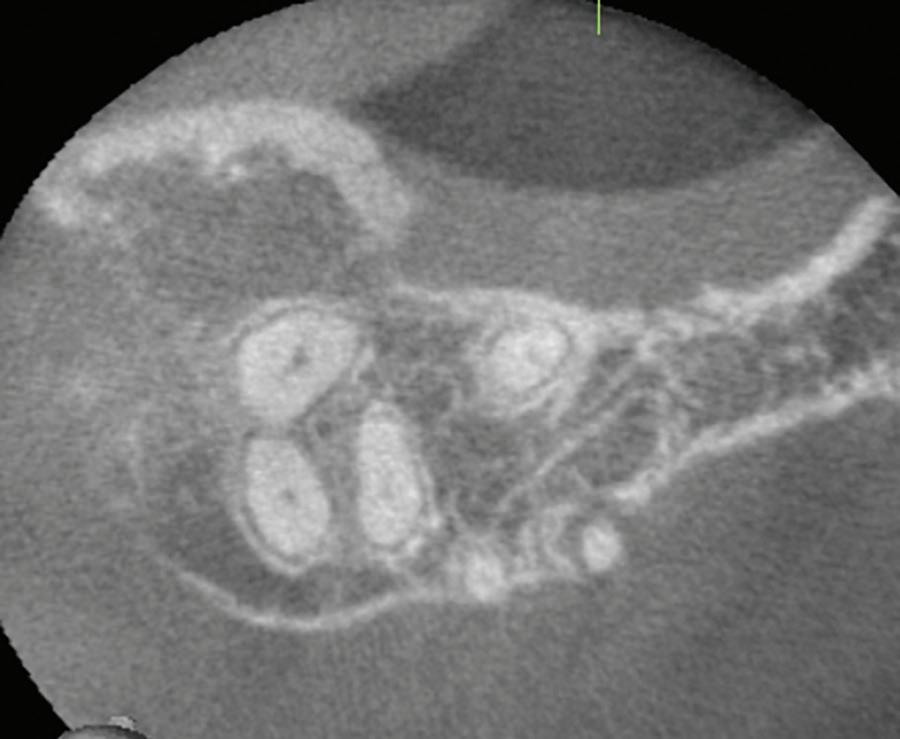

Fig 1. Proximity of root apices to vital structures. A. The periapical radiograph indicates that the apices of the mandibular right second molar and second premolar are in proximity to the inferior alveolar and mental nerves. B. A coronal CBCT image more clearly demonstrates the proximity of the molar apex to the inferior alveolar nerve. C. A coronal CBCT image more clearly demonstrates the proximity of the premolar apex to the mental nerve.

The inferior alveolar canal courses closely beneath the apices of mandibular molars, particularly second molars. Studies have shown that in more than 25% to 30% of patients, the inferior alveolar canal lies within 1 mm of the root apices of second molars; the prevalence is even higher in female and older patients due to reduced bone volume (Fig 1).8

Cone beam computed tomography

CBCT has revolutionized endodontic diagnostics by allowing practitioners to evaluate dental anatomy in 3 dimensions (3D). In contrast to traditional 2D radiographs, CBCT images can reveal nuances such as root canal curvature, apical deltas, external resorptions, fenestrations, and anatomical landmarks

that would otherwise go unnoticed. The ability to visualize the thickness of cortical bone, the position of the inferior alveolar canal, or the floor of the maxillary sinus can alter treatment decisions dramatically. For example, in cases where apical surgery is being considered, evaluation of CBCT images can determine whether the apex is embedded in the sinus or the mandibular canal is at risk of involvement.

The American Association of Endodontists and the American Academy of Oral and Maxillofacial Radiology jointly recommend the use of CBCT in select cases involving complex root canal anatomy, persistent periapical pathosis, or surgical planning.26 These guidelines emphasize CBCT as an adjunct, not a routine imaging modality, primarily to limit unnecessary radiation exposure and ensure judicious use of advanced diagnostics. Some clinicians have argued that concerns over CBCT radiation dosage may be overstated, particularly when weighed against the diagnostic and safety benefits in complex cases.27

It also could be argued that the potential for iatrogenic complications, including extrusion-related nerve injuries or sinus involvement, supports a more universal application of preoperative CBCT, especially in posterior teeth or anatomically high-risk zones. For instance, bony fenestrations, which create direct communication between the root surface and soft tissue due to absence of cortical bone, are virtually invisible on standard 2D radiographs. These defects significantly increase the risk of overinstrumentation; endodontic irrigant and obturation material extrusion; and postoperative inflammation, particularly when the root apex lies adjacent to neurovascular structures or sinus cavities. CBCT is the only reliable tool to detect fenestrations preoperatively. It allows visualization of cortical bone thickness and can identify discontinuities in the buccal or lingual plate that predispose to soft tissue perforation (Fig 5).